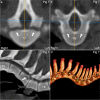

Background: Computed tomography (CT) is used to evaluate body composition and limb osteochondrosis in selection of breeding boars. Pigs also develop heritably predisposed abnormal curvature of the spine including juvenile kyphosis. It has been suggested that osteochondrosis-like changes cause vertebral wedging and kyphosis, both of which are identifiable by CT. The aim of the current study was to examine the spine from occiput to sacrum to map changes and evaluate relationships, especially whether osteochondrosis caused juvenile kyphosis, in which case CT could be used in selection against it. Whole-body CT scans were collected retrospectively from 37 Landrace or Duroc boars with poor back conformation scores. Spine curvature and vertebral shape were evaluated, and all inter-vertebral, articular process and rib joints from the occiput to the sacrum were assessed for osteochondrosis and other lesions.

Results: Twenty-seven of the 37 (73%) pigs had normal spine curvature, whereas 10/37 (27%) pigs had abnormal curvature and all of them had wedge vertebrae. The 37 pigs had 875 focal lesions in articular process and rib joints, 98.5% of which represented stages of osteochondrosis. Five of the 37 pigs had focal lesions in other parts of vertebrae, mainly consisting of vertebral body osteochondrosis. The 10 pigs with abnormal curvature had 21 wedge vertebrae, comprising 10 vertebrae without focal lesions, six ventral wedge vertebrae with ventral osteochondrosis lesions and five dorsal wedge vertebrae with lesions in the neuro-central synchondrosis, articular process or rib joints.

Conclusions: Computed tomography was suited for identification of wedge vertebrae, and kyphosis was due to ventral wedge vertebrae compatible with heritably predisposed vertebral body osteochondrosis. Articular process and rib joint osteochondrosis may represent incidental findings in wedge vertebrae. The role of the neuro-central synchondrosis in the pathogenesis of vertebral wedging warrants further investigation.